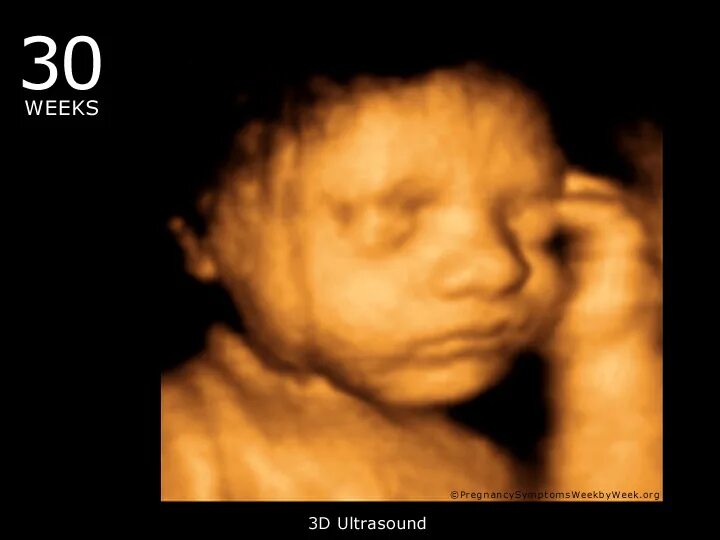

Девочка 30 недель